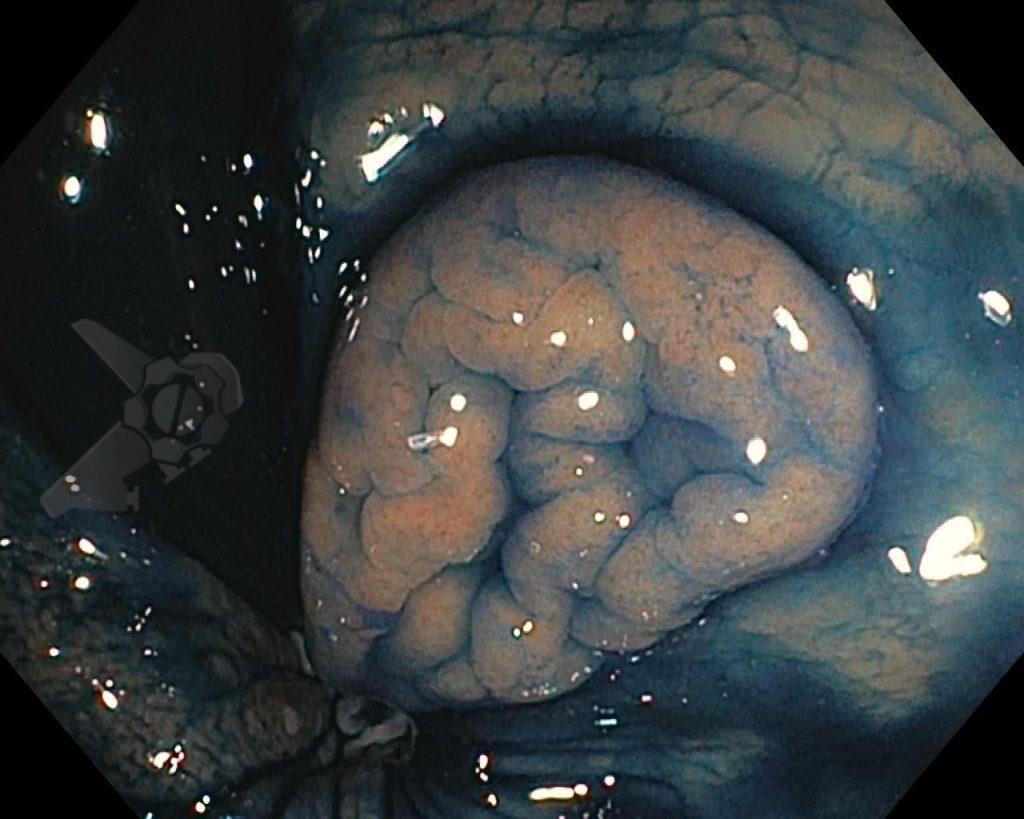

Paciente do sexo feminino, 54 anos, hipertensa, com relato de um episódio de hematoquezia ocorrido há 30 dias. Nega perda ponderal ou alteração do hábito intestinal. Realizou colonoscopia, sendo identificada, em reto distal, próximo à linha pectínea, lesão mostrada abaixo medindo cerca de 2 cm.

Foi realizada cromoscopia com índigo carmim e biópsias.